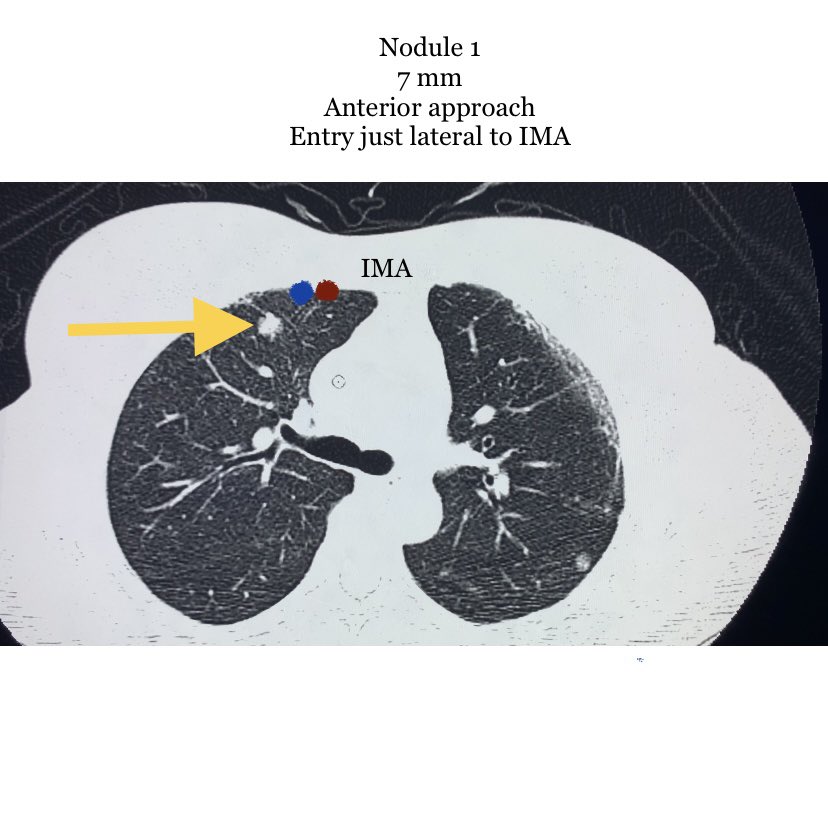

@evascularrounds @bhavinj @SRajesh_IR @No_cut_surgery @keithppereira @lenonjdee @_backtable @Dr_AkshayBaheti @SandeepBaglaMD @iRadRock @TomG_IR @Watts_IR @IrShaileshgupta @vascularIR Agreed, I would go for #4. Large enough to get adequate tissue, peripheral enough to limit risks. While I often like anterior approaches to enable supine positioning, the breast tissue, IMA, and small nodule size make #1 a little more complicated.

Reference for CT guided lung lesion biopsy. Nodule preference for biopsy and why?

Nodule 1, 2, 3 or 4?

@bhavinj @SRajesh_IR @No_cut_surgery @keithppereira @lenonjdee @_backtable @Dr_AkshayBaheti @SandeepBaglaMD @iRadRock @TomG_IR @Watts_IR @IrShaileshgupta @Golden_IR @vascularIR